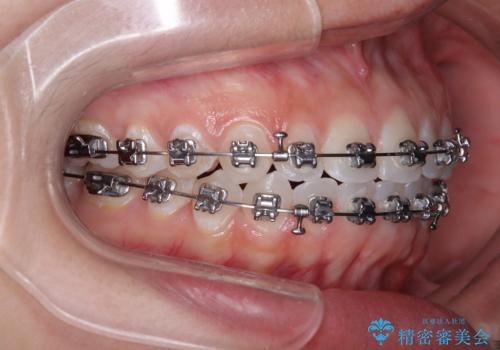

【モニター】マウスピース矯正が煩わしい ワイヤー装置での非抜歯矯正

- 矯正装置

- メタルブラケット

- 上下前歯のデコボコを気にして来院された患者様です。

ワイヤー矯正でもマウスピース矯正でも可能でしたが、短期間で、自身の手を煩わせることなく治療を行いたいとのことで、ワイヤー装置にて矯正治療を行うこととしました。

僅か半年強、あっという間に治療を終えることができました。